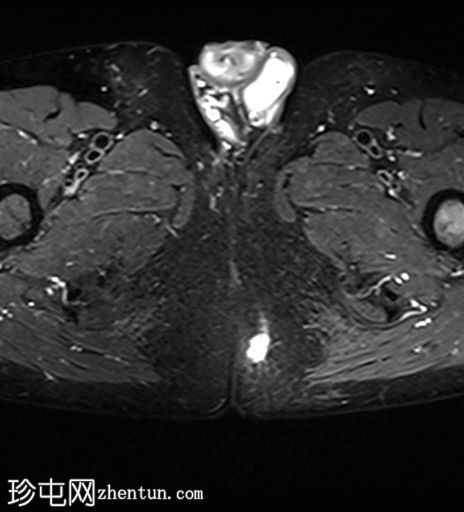

轴向位

T1

位于5点钟和6点钟位置之间,在STIR和T2加权图像上呈高信号。

瘘管起源于括约肌间平面附近,穿过肛门内外括约肌,并延伸至左侧坐骨肛门窝。瘘管内充满液体信号,周围有轻微水肿。肛提肌上方未观察到颅骨延伸。

根据圣詹姆斯大学医院的磁共振分类系统,该病例被归类为III级左侧肛周经括约肌瘘,左侧坐骨肛门窝可见炎症改变。